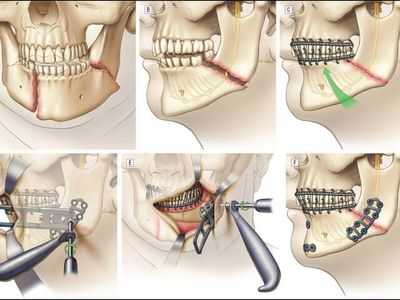

Хирургическое вмешательство. Смещение отломков осложняются мышечной интерпозицией, что является прямым показанием к остеосинтезу.

Существуют различные способы внутрикостного и накостного оперативного закрепления отломков нижней челюсти и их сочетаний, фиксирующее отломки устройство может соединять их концы, пересекая щель перелома, проходя внутри кости.

Оно может прилежать к ее компактной пластинке или частично входить в кость (прямой остеосинтез). Прямой остеосинтез предполагает рассечение мягких тканей и обнажение концов костных отломков (за исключением закрытого введения спиц) с последующим ушиванием раны наглухо. Фиксирующее приспособление полностью закрыто мягкими тканями.

Приспособление для остеосинтеза может быть наложено на костные фрагменты на расстоянии от щели перелома и закреплено вне костной раны (непрямой остеосинтез). При непрямом остеосинтезе оно всегда выходит через кожу или слизистую оболочку полости рта наружу. Скелетирование (обнажение) отломков при этом проводят значительно реже, чем в случае прямого остеосинтеза.